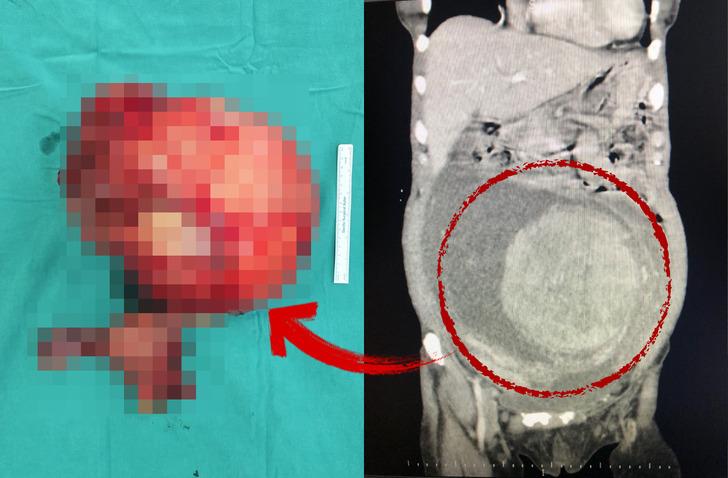

Tokat Devlet Hastanesi'nde görevli Genel Cerrahlar Operatör Doktor Ahmet Topcu ve Orkun Subaşı, Hicran Işık tarafından gerçekleştirilen başarılı ameliyatla, Işık'ın yumurtalıklarından 30x25 santim boyutlarında ve 6 kilogram ağırlığında kitle çıkarıldı.